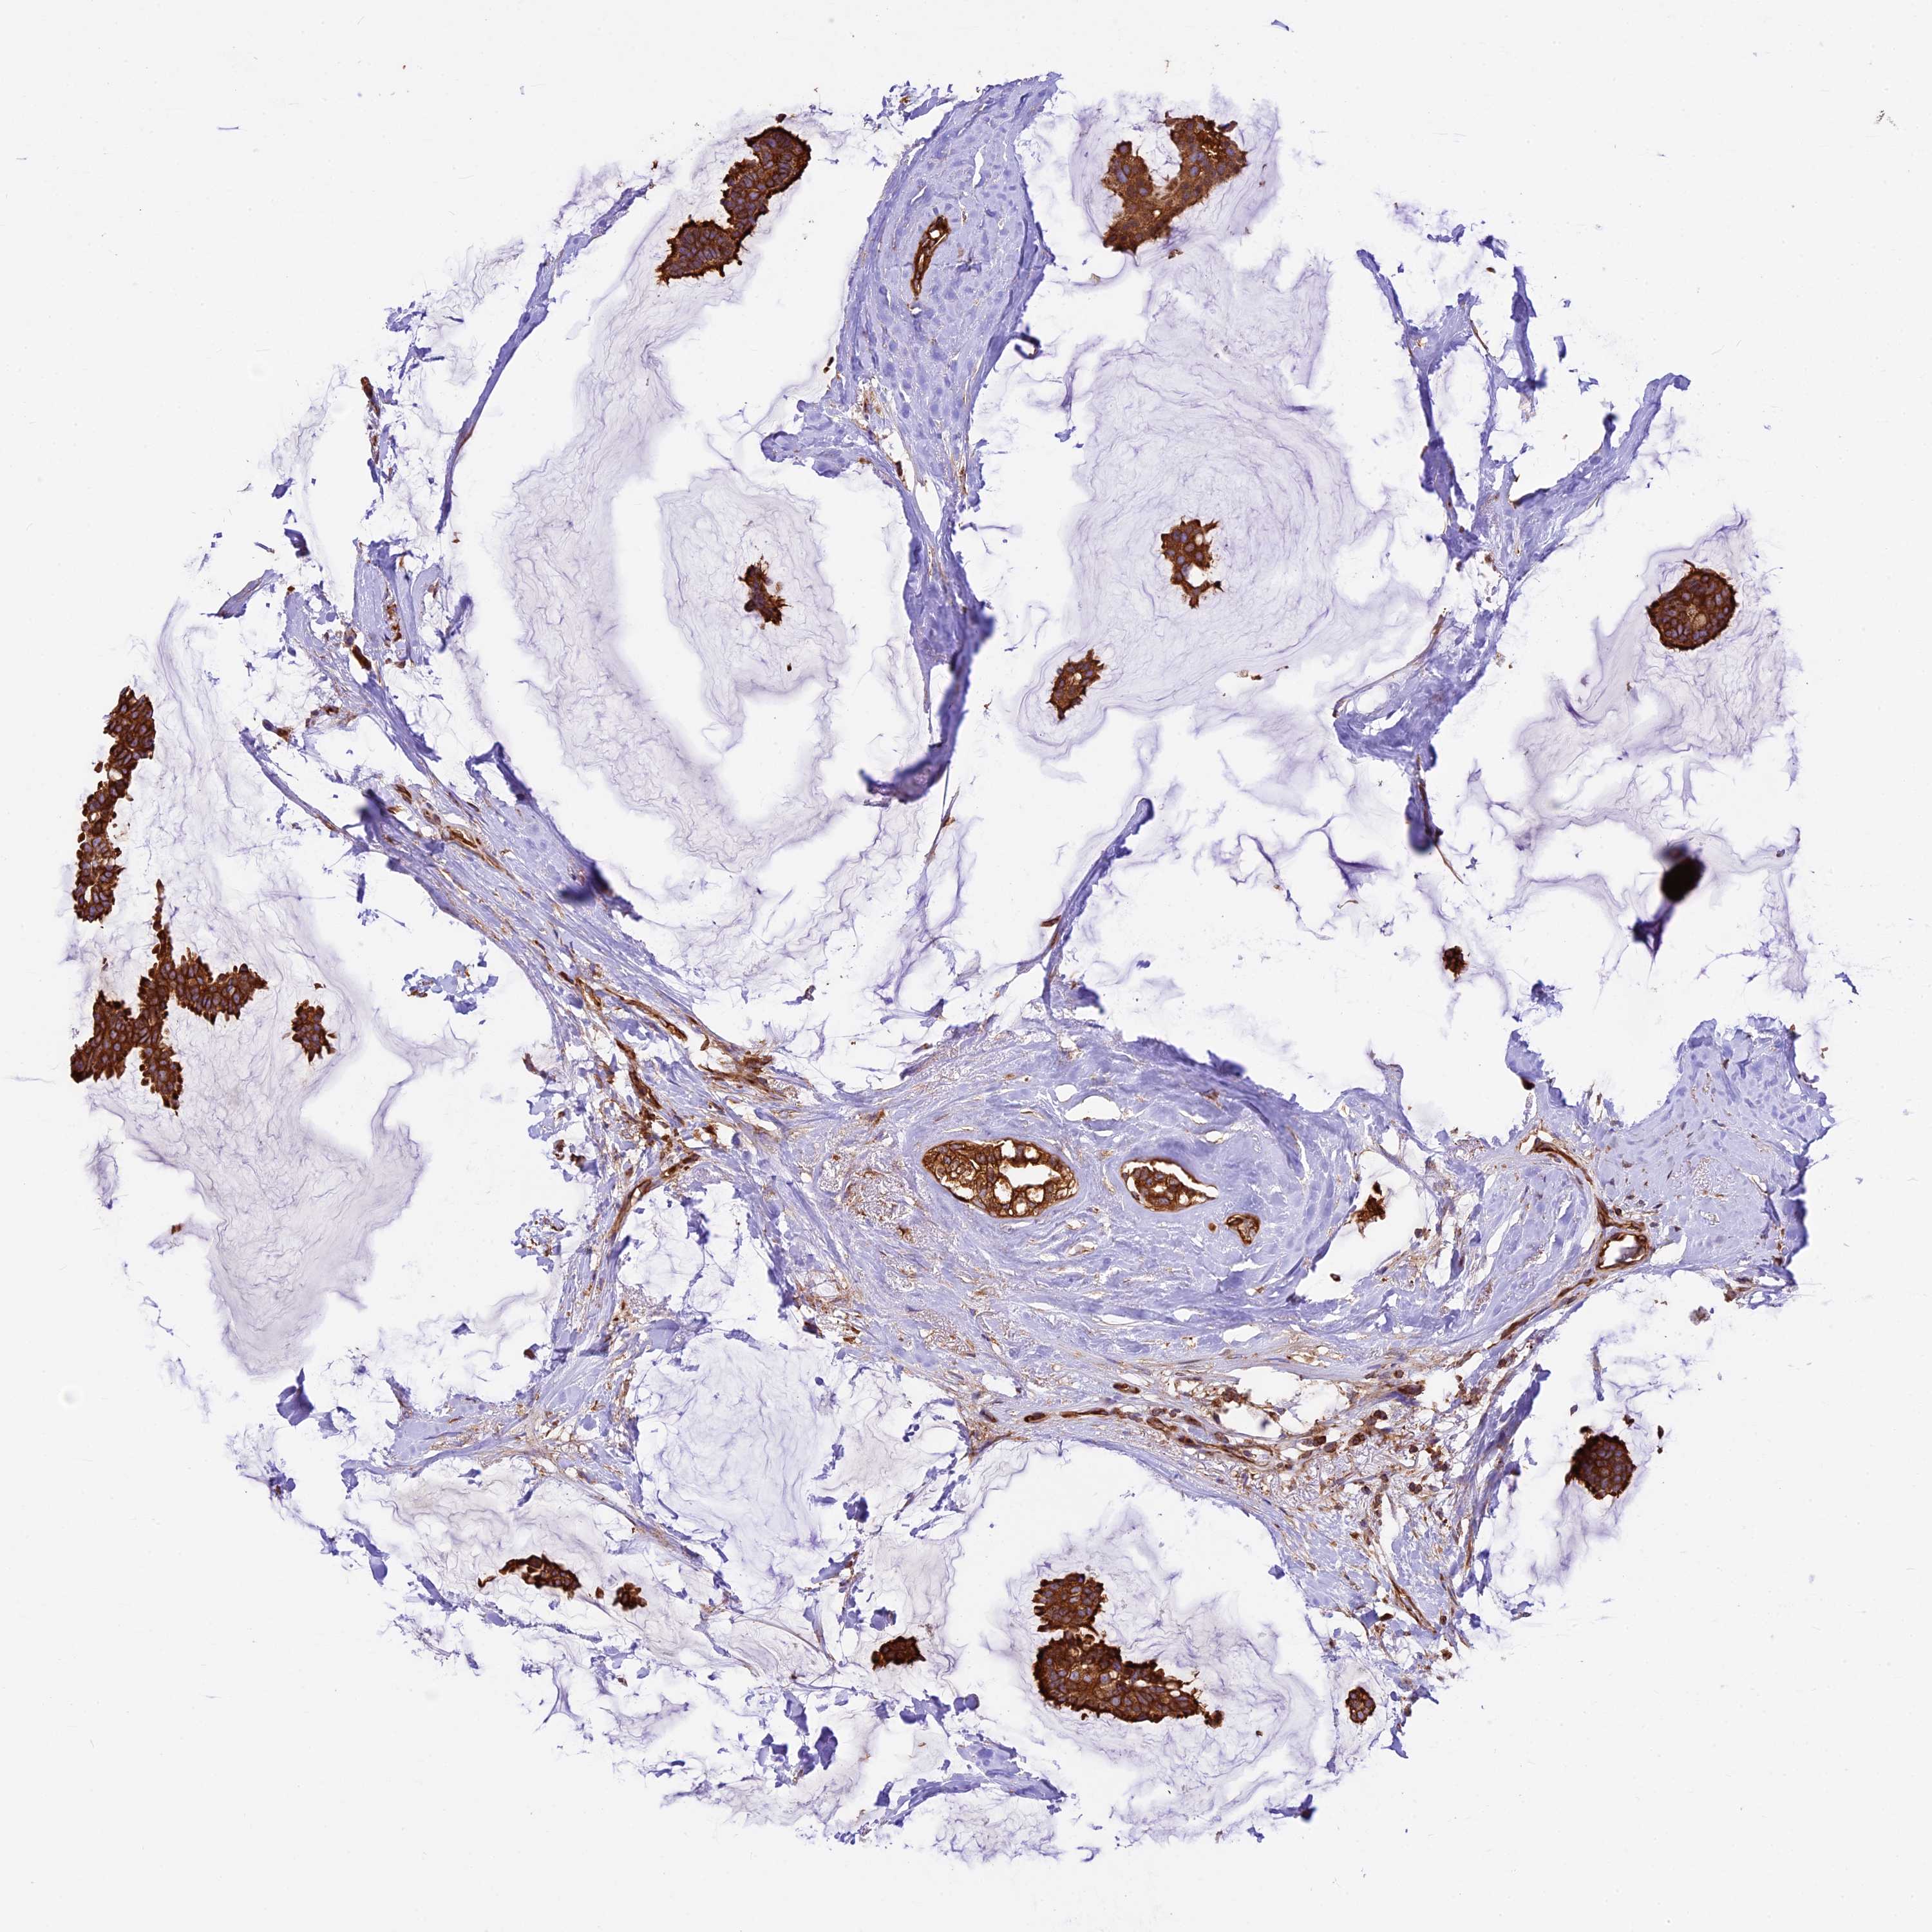

CANCER BREAST CANCER Show tissue menu

BRCA TCGA BRCA VALIDATION PROTEIN EXPRESSION